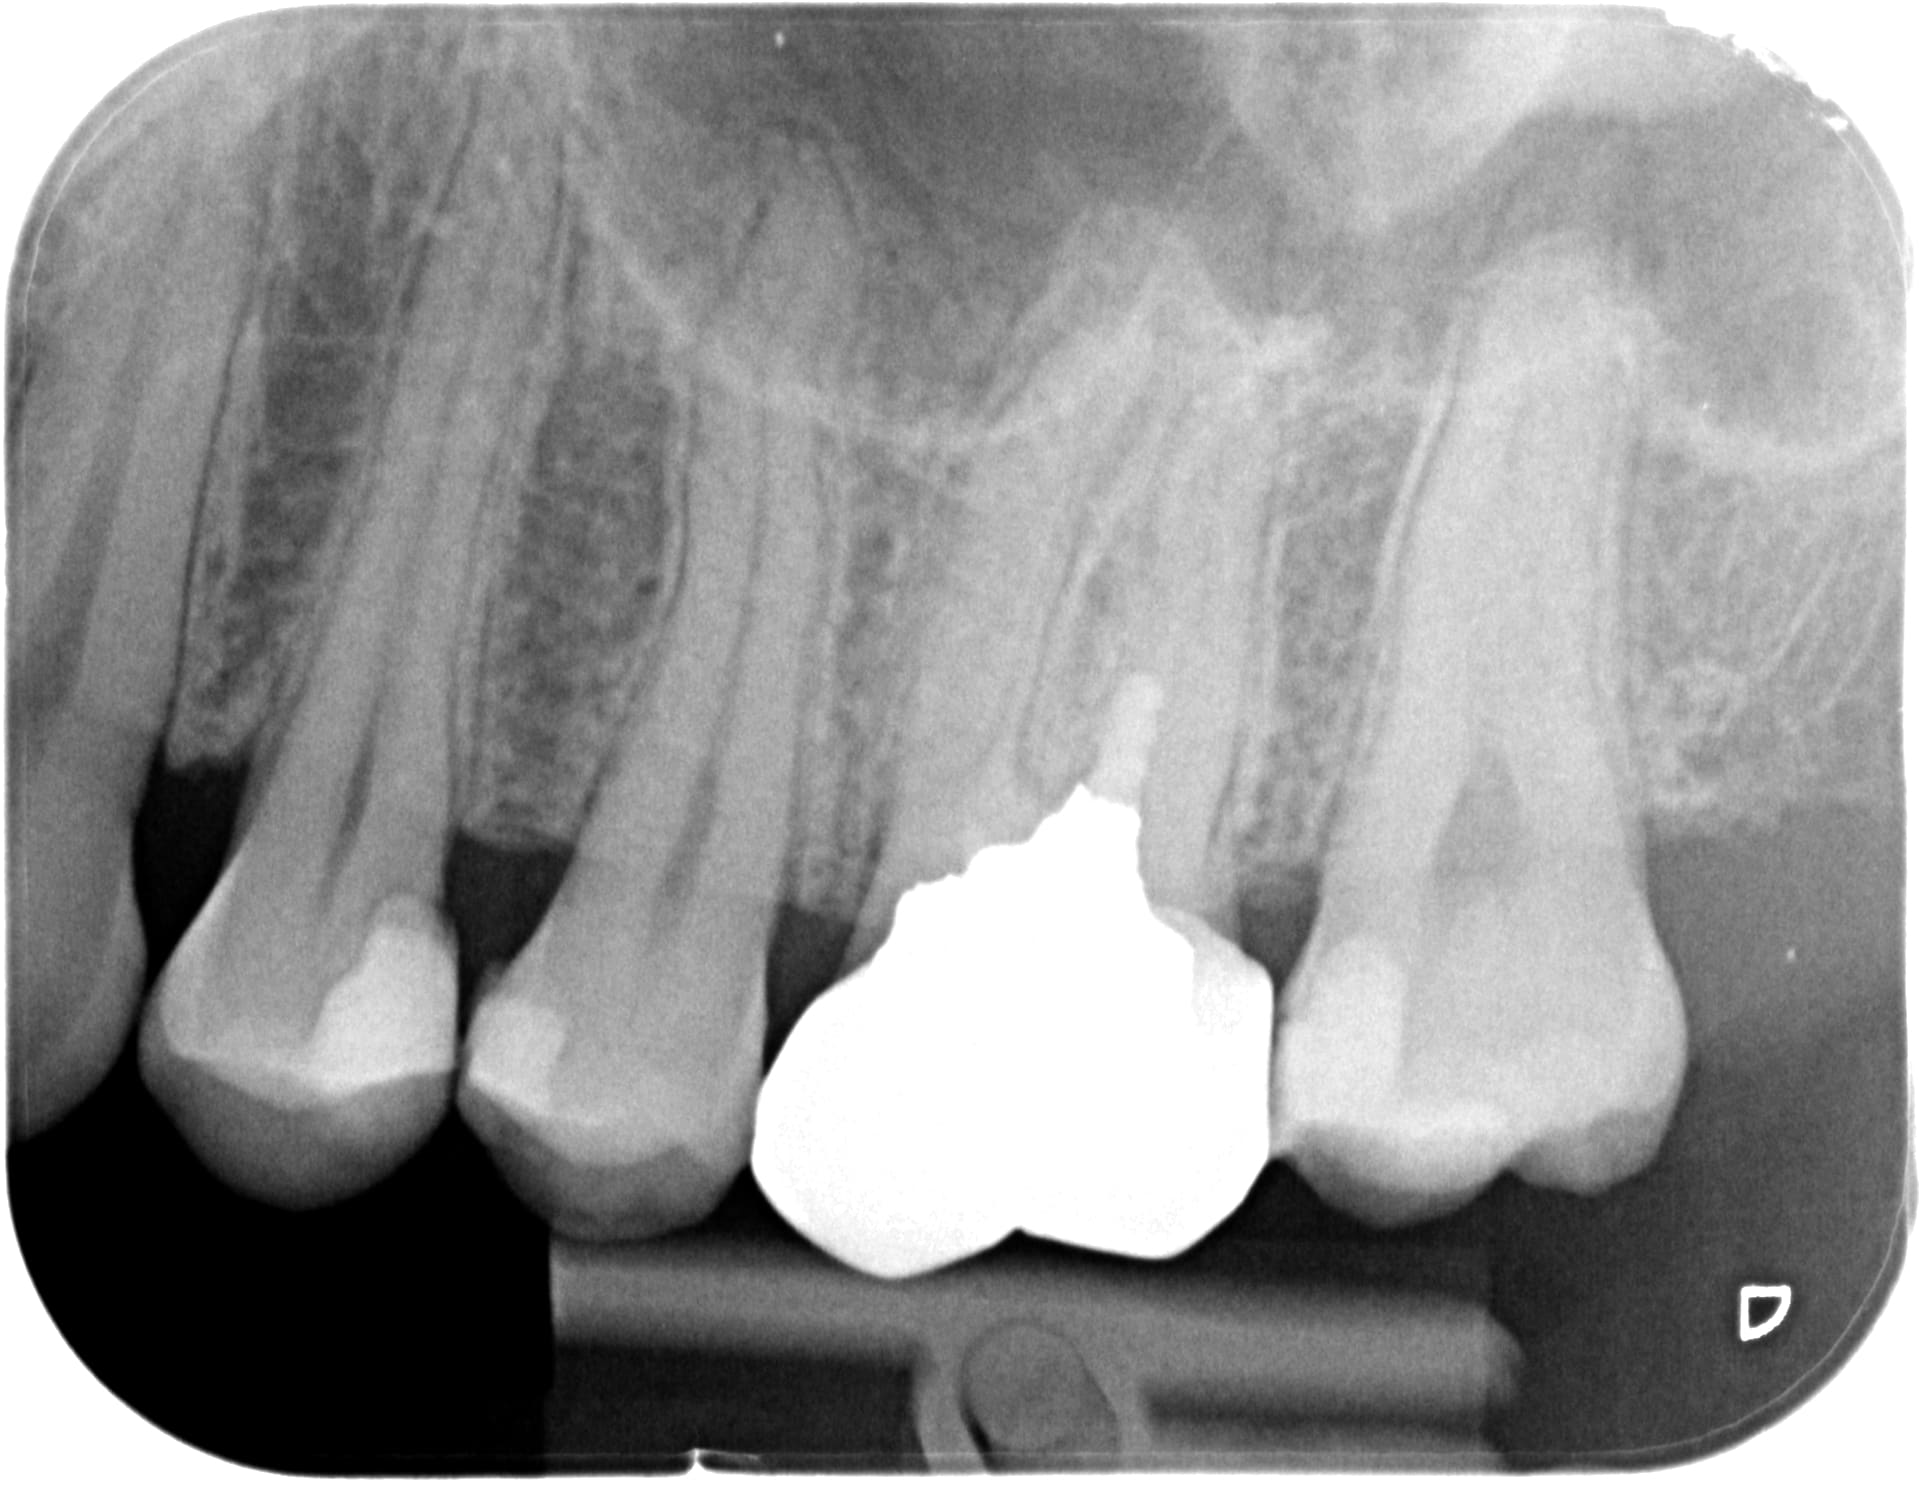

La par exemple, même a 410e la coiffe ceram mon confrère a été rentable.

Nouveau patient, motif: couronne descellée sur 13.

heureusement qu'il reste un peu de NPC pour refaire ;)

jusqu'a quand ???

En cadeau bonus... la 26 d'une jeune de 30 ans.

Meme a 250e la coiffe tu gagnes du pognon... 2 RDV de 10 min.